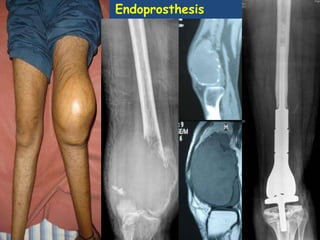

Endoprosthesis

T – Construct reconstruction